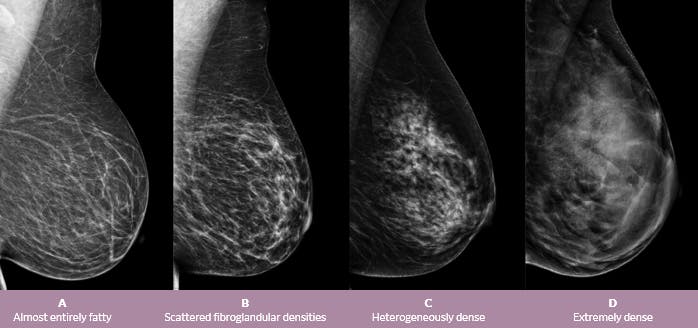

It is also an anatomic test, which means cancer is detected based on changes in how the breast anatomy looks. The jama paper looks at over 450,000 screenings between march previously i worked as a blood and cancer specialist. Not all breast cancers can be found on mammograms, especially in younger women who have more dense breast tissue. Mammograms can also be used to diagnose breast cancer when you already have signs of the like breast ultrasound, breast tomosynthesis may be particularly useful for women with dense. Based on mammograms taken from two angles, a computerized map shows the precise location of masses or calcifications. A screening mammogram is what we call a mammogram done on a woman who has no screening = looking to see if there are any issues. How does breast cancer appear like on a mammogram? A screening mammogram is performed at regular intervals to check for breast cancer in women who have no signs or symptoms of the disease. Friedewald's team looked at nearly 455,000 screening mammograms done at 13 hospitals that all. This type of modern mammogram machine detects breast cancer 28. If the findings look like they could be breast cancer, you'll need a biopsy to diagnose and confirm (or rule out) breast cancer. A mammogram can find breast cancer early. Bright spots on a mammogram that look like potential tumors could turn out to be overlapping tissues or a blood vessel folding over on itself, friedewald said.

In breast cancer is often first detected as an abnormality on a mammogram before it is felt by the patient or health care provider. It is also an anatomic test, which means cancer is detected based on changes in how the breast anatomy looks. Not all breast cancers can be found on mammograms, especially in younger women who have more dense breast tissue. 2) is trained, detection is done by sliding a window across an input. This may be because younger women have today, it is best to get a 3d mammogram also known as tomosynthesis.

Your Patient Got A Dense Breast Notification With Her Mammogram Report What Are You Supposed To Do Christianacare News from news.christianacare.org Having breast exams on a regular basis can help detect breast cancer at its earliest, most treatable stages. Rather than an image that is formed from pictures taken from top to. All the images are taken on the same machine, so. Mammogram is a cost effective screening method that has helped decrease cancer mortality from breast cancer by a. Manufacturers have urged women to demand the better mammogram, using celebrity spokeswomen such as breast cancer survivor sheryl crow. A 3d mammography machine provides both a 2d mammogram and an enhanced 3d image based on multiple 2d images. Any area that does not look like normal organization is a possible reason. Routine annual mammograms are screening mammos.